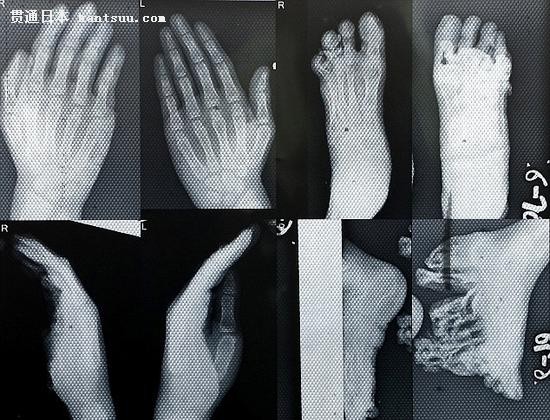

3姐妹脚掌像树皮 像极了日本的木屐鞋子

脚掌 据悉,手术成功移除了三姐妹脚掌的肿瘤,术后一个月,三姐妹终于 踏出了独立行走的第一步。“双胞胎妹妹们已经能够自信行走,姐姐走路时仍有痛感,但是也会日渐好转。”纳亚克博士说道。她们的父母也对此欣喜万分。“看到 她们能够站起来,自己独立走路,我真的是太高兴了。”父亲塞蒂说道,“我希望有朝一日,能够送她们去上学。” 目前三姐妹仍在留院观察。纳亚克博士表示,如果皮肤感染复发,三姐妹还需再次接受手术治疗。 |